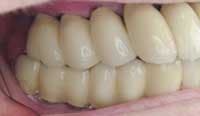

Photos of same woman after implant restoration

The case above is an excellent example in which someone who experiences continued periodontal breakdown around teeth despite treatment will fare better with implants and resist problems with future decay. Dr. Andrew Alpert of Aventura, Fla., placed the implants.

To help a patient understand the benefits of implant restoration, show before and after images of another patient and talk about the stability and improved esthetics achieved.